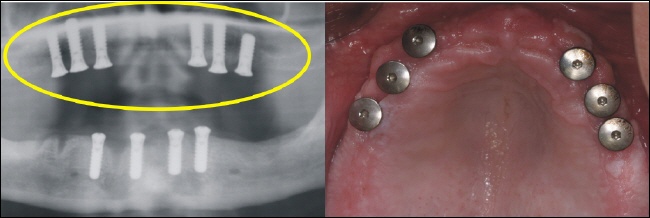

Nach der Einheilzeit werden auf die Implantate Teleskopkronen aufgesetzt, über die der Zahnersatz gesteckt wird (Oberkiefer). |

Nach der Einheilzeit werden auf die Implantate Teleskopkronen aufgesetzt über die der Zahnersatz gesteckt wird (Unterkiefer). |